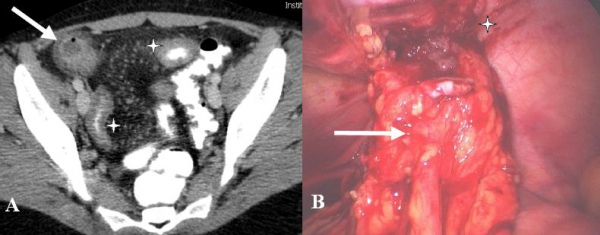

Hình 26: Túi thừa Meckel lộn ngược ở bệnh nhân nam 31 tuổi. A, CT uống và tiêm cản quang, thấy khối lồng hồi manh tràng, có “target sign” (đầu mũi tên). B, Vùng trung tâm là lõi dài đậm độ mỡ (mũi tên. Sau mổ là túi thừa Meckel lộn ngược . (Angela D. Levy, Christine M. Hobbs (2004). Meckel Diverticulum: Radiologic Features with Pathologic Correlation. RadioGraphics 24:583).